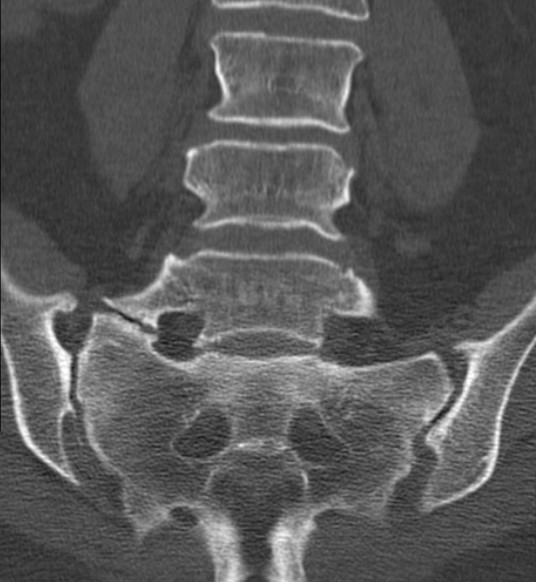

SÍNDROME DE BERTOLOTTI

La columna vertebral es un prodigio estructural y funcional constituido como mecanismo de soporte y protección para las…